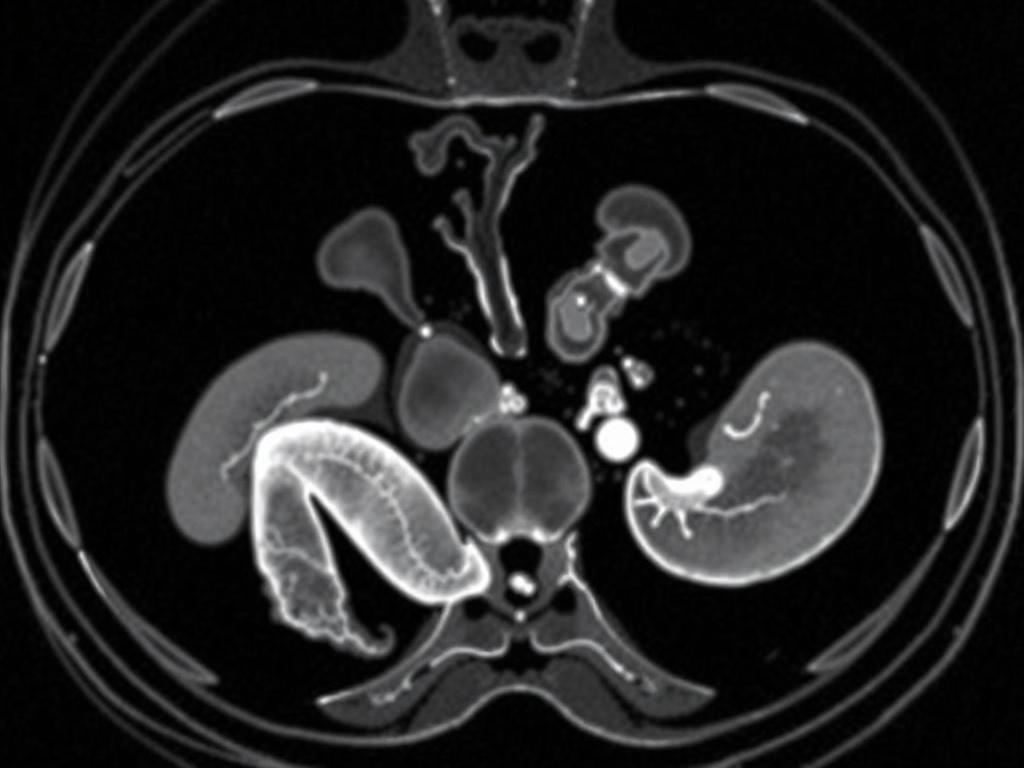

Аномалии почек и мочевых путей нередко диагностируются при пренатальном УЗИ и варьируют от бессимптомных до требующих оперативного вмешательства. Некоторые пороки приводят к нарушениям функции и повышенному риску инфекций, поэтому ранняя оценка и наблюдение обязательны. Более редкие генитальные аномалии ставят вопросы о половой идентификации и требуют участия эндокринолога и психолога.

Терапия зависит от природы дефекта: от консервативной коррекции до реконструктивных операций. Долгосрочный мониторинг функции почек, контроля артериального давления и качества жизни должен вестись системно. Важна открытая и деликатная коммуникация с семьёй при принятии решений, которые могут повлиять на будущее ребёнка.

Современная диагностика сочетает ультразвук, биохимические скрининги, неинвазивное пренатальное тестирование и при необходимости инвазивные процедуры, такие как амниоцентез. Пренатальная диагностика даёт шанс раннего вмешательства, подготовки родов и планирования лечения после рождения. Она также важна для информированного принятия решений родителями и врачами.

После рождения используется клинический осмотр, УЗИ, рентген, КТ и МРТ для уточнения анатомии, а также генетические тесты при подозрении на наследственные синдромы. Комплексная оценка позволяет составить индивидуальный план лечения и реабилитации. Чем раньше начата адекватная оценка, тем шире спектр доступных вмешательств и часть рисков можно минимизировать.